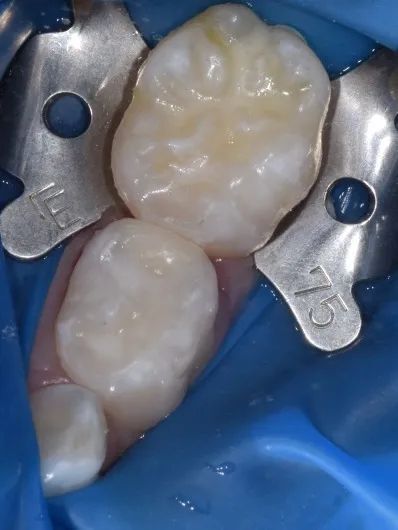

以常见的“树脂基质窝沟封闭剂”为例,其流程大致包括:清洁牙面、隔湿、酸蚀、冲洗干燥、涂布粘结剂、光固化、检查。1次隔湿(如下图),通常可做1-2颗牙,或邻近的多颗牙,操作下来需要5-10分钟。窝沟封闭的时间,主要取决于需要隔湿几次。